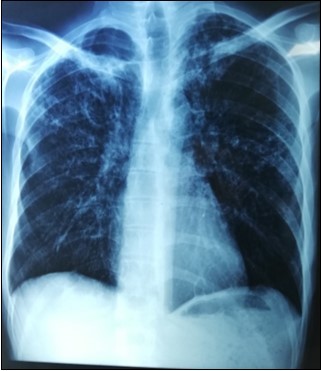

Abdomen and chest radiography showed pneumoperitoneum (Figure 1).

Figure 1.Pneumoperitoneum on chest X Ray